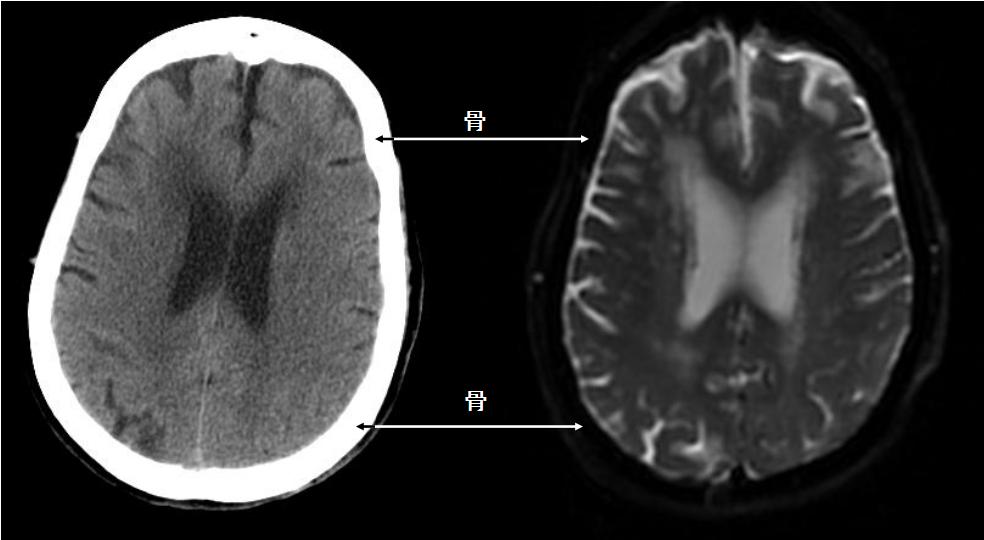

头颅CT、MRI图像对比

CT检查是断面显像,没有重叠盲区,成像速度快,而且是密度分辨力最高的影像学检查方法,对于诊断复杂部位的骨折、脑出血、胸部、腹部和骨关节的进一步检查等都很适用。

MRI(磁共振)检查同样是可以多方向断面成像的优秀检查方法,具有非常强的软组织分辨力,还具有多参数成像、功能成像手段丰富等特点,其应用范围越来越广,特别是对于神经系统(脑、脊髓)、腹部、关节内结构和头颈部软组织等病变显示的敏感度和特异度均较高。但由于其成像时间较长、费用较高,对钙化灶、骨骼以及肺部病灶的显示相对较差,强大磁场对体内金属异物的吸引及热效应等,也限制了其应用。